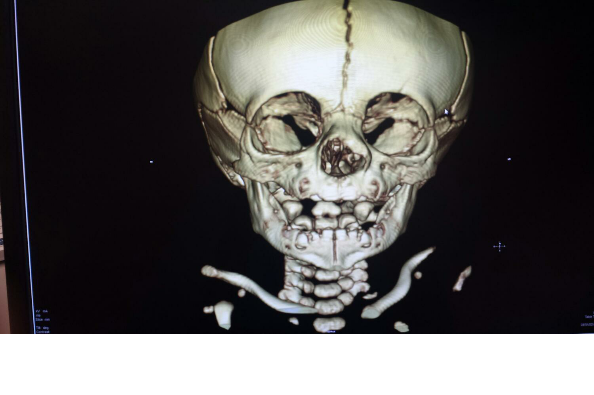

The news was the worst news that could have been given, confirmed. The mass was a tumor with an extension attaching to his brain. It was called a Glioma Tumor. Glioma Tumors are made up of glial cells, which are supportive cells that help the brain cells function.

Because he had developed the tumor in the womb, it had also stopped the normal growth of the bone in his nose. He was now required to have two separate surgeries. The earliest they would be able to do the first surgery on Jaxson, would be when he turned 6 months old. For him, this would mean December 2014 and then his second surgery, they'd do a few months later.

On September 25th the Neurosurgeon delivered good news and more bad news. The bad news was that Jaxson's tumor is extremely rare in the fact that it grew through his sinus cavity. There have only been 1 or 2 reported cases in the whole Northwestern Hemisphere. The good news was that although she has never seen this type of tumor, she had scrubbed in on a few that had grown from the base of the neck while interning. She was very confident about the procedure (bi-frontal craniotomy & resection of nasal glioma with intracranial extensions) and her ability to remove the tumor successfully. She did however add one more risk factor to the surgery. She said that the hardest part of the surgery she is performing, is insuring that no brain fluid is leaked while she is removing the tumor.

The news was the worst news that could have been given, confirmed. The mass was a tumor with an extension attaching to his brain. It was called a Glioma Tumor. Glioma Tumors are made up of glial cells, which are supportive cells that help the brain cells function.

Because he had developed the tumor in the womb, it had also stopped the normal growth of the bone in his nose. He was now required to have two separate surgeries. The earliest they would be able to do the first surgery on Jaxson, would be when he turned 6 months old. For him, this would mean December 2014 and then his second surgery, they'd do a few months later.

On September 25th the Neurosurgeon delivered good news and more bad news. The bad news was that Jaxson's tumor is extremely rare in the fact that it grew through his sinus cavity. There have only been 1 or 2 reported cases in the whole Northwestern Hemisphere. The good news was that although she has never seen this type of tumor, she had scrubbed in on a few that had grown from the base of the neck while interning. She was very confident about the procedure (bi-frontal craniotomy & resection of nasal glioma with intracranial extensions) and her ability to remove the tumor successfully. She did however add one more risk factor to the surgery. She said that the hardest part of the surgery she is performing, is insuring that no brain fluid is leaked while she is removing the tumor.